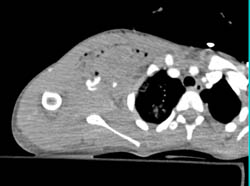

Calcifications in Breast Due to Worm- Cysticercosis